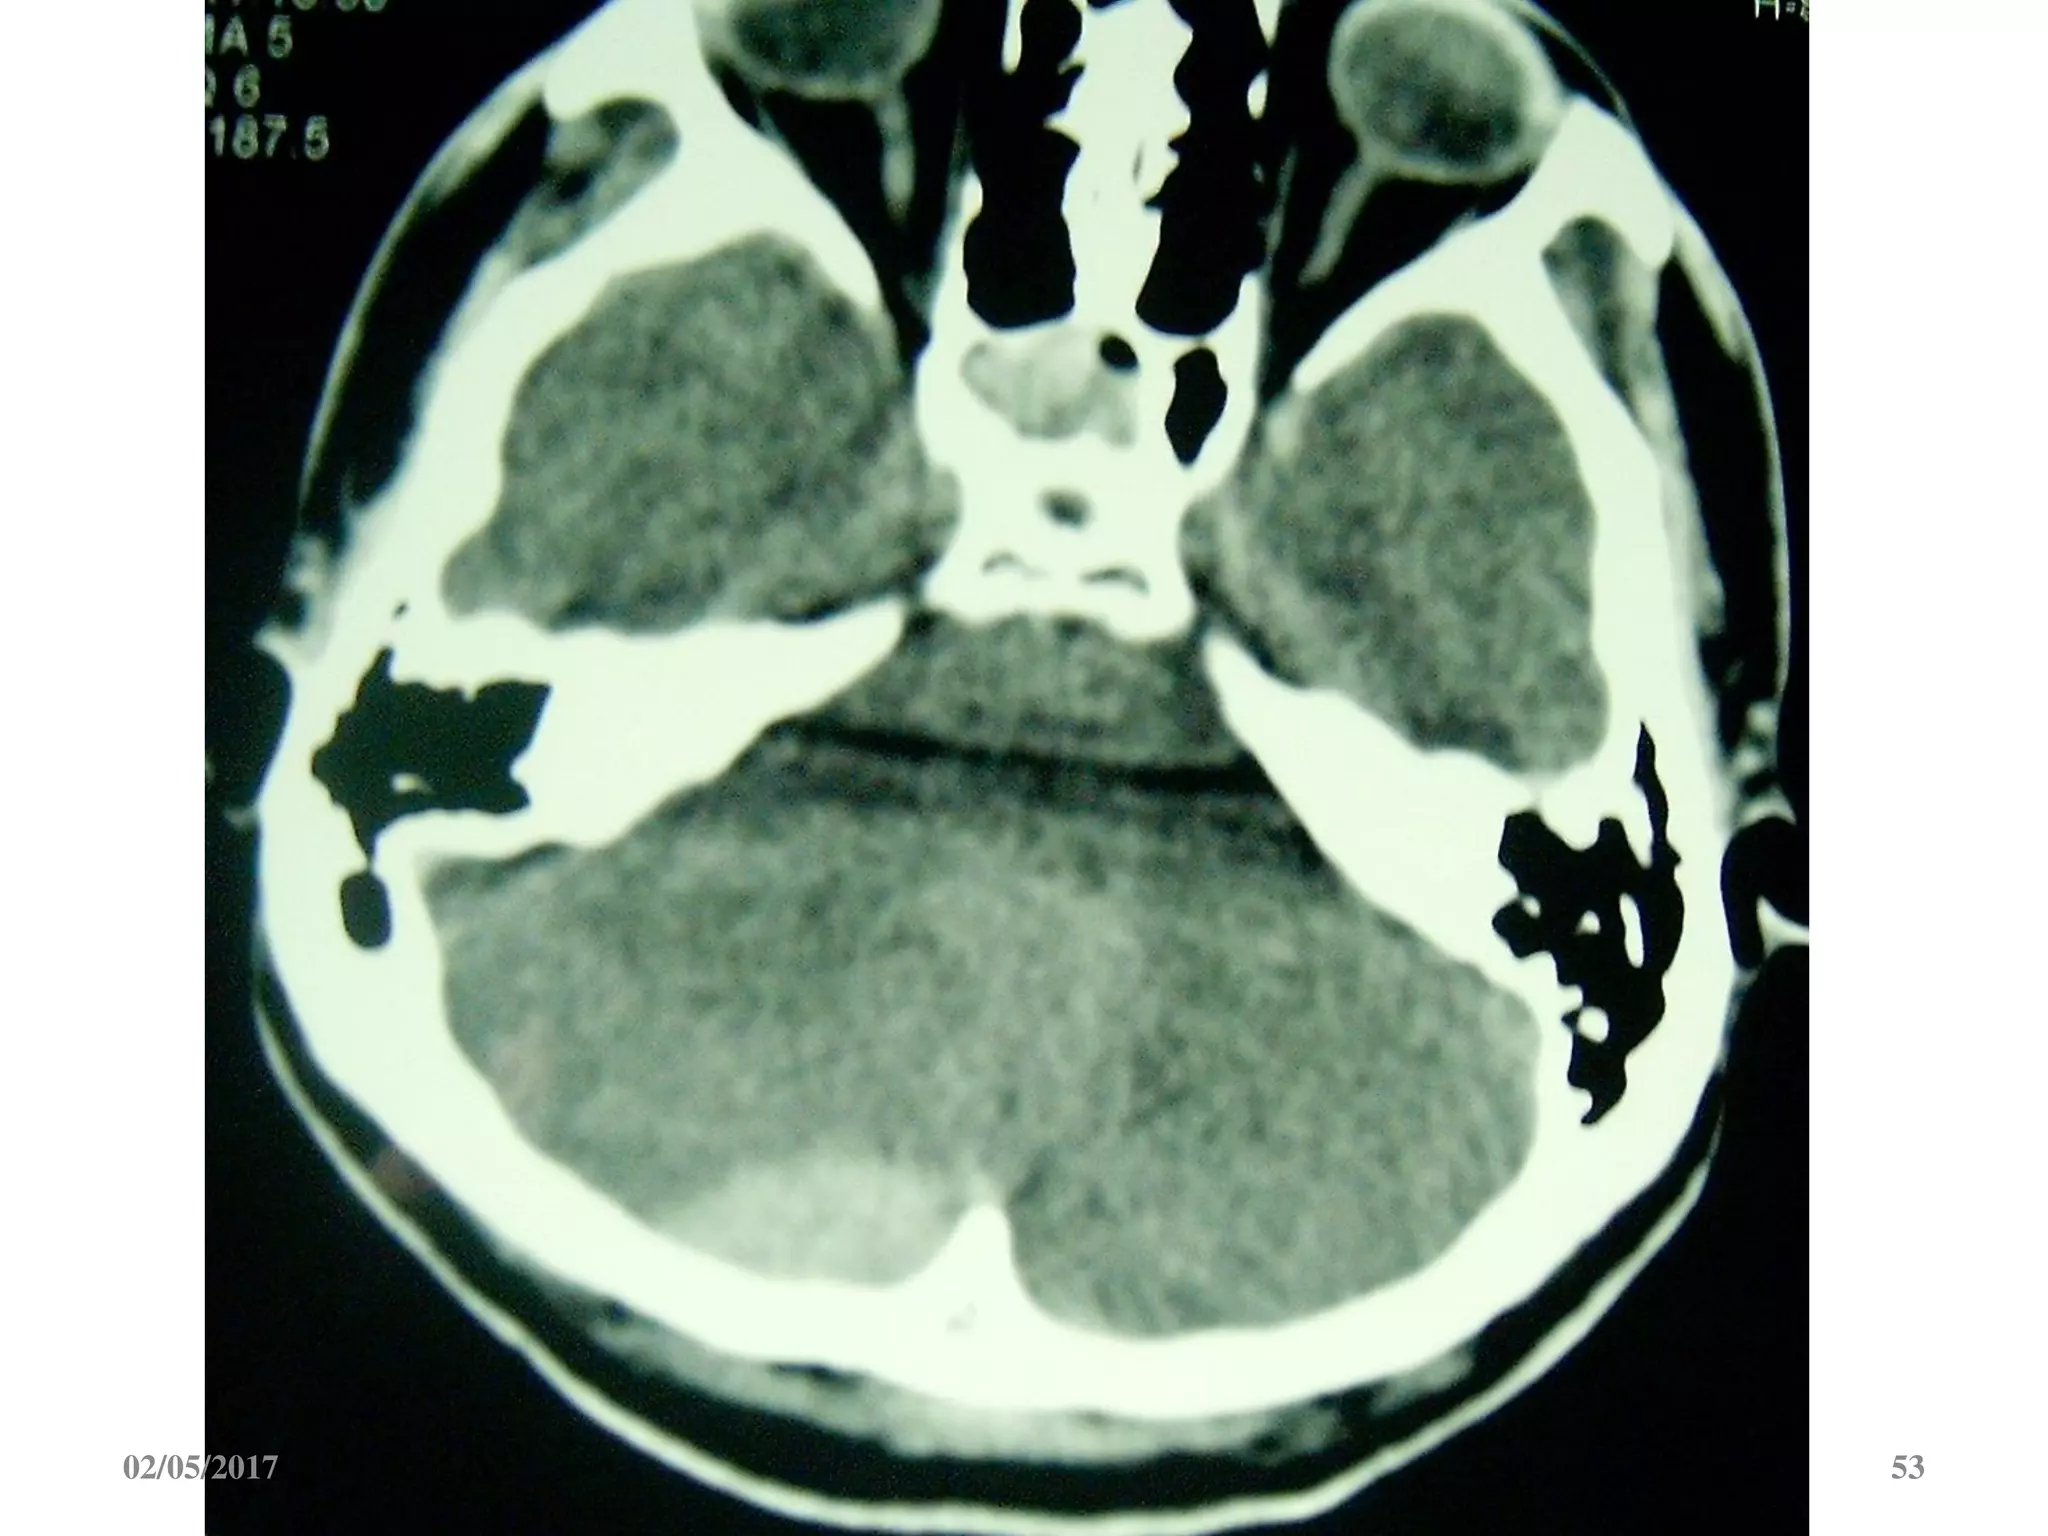

 Máu tụ hố sau gây chèn ép não thất 4.

3. Máu tụ hố sau: xóa mất, đẩy lệch não thất 4